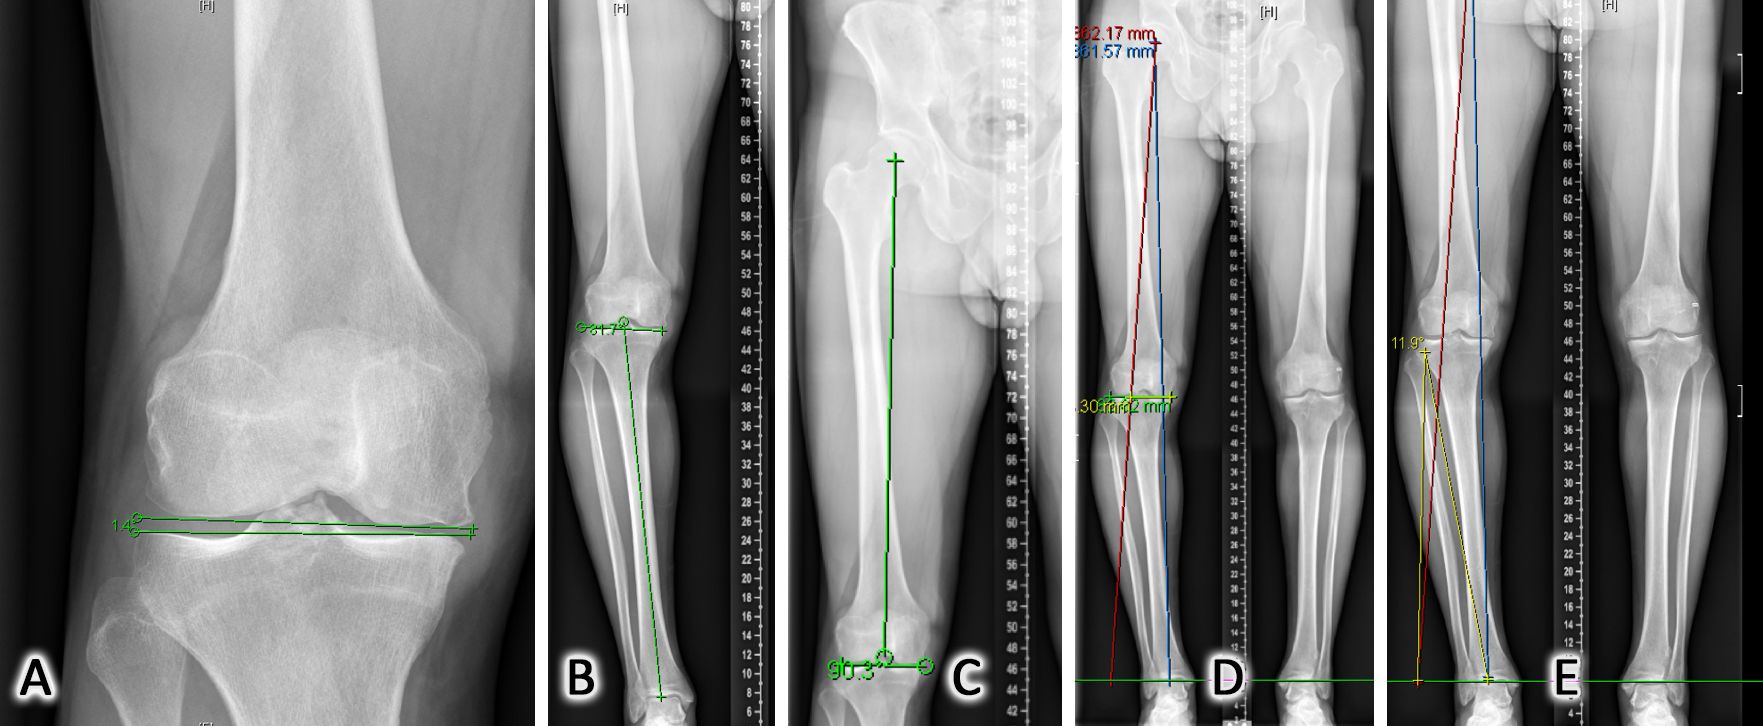

The clinical articles in this issue span several interconnected domains. In traumatology, a structured diagnostic algorithm is presented for acute syndesmotic injuries, commonly referred to as high ankle sprains, integrating clinical history, physical examination, and imaging findings. Attention then turns to lower limb alignment in arthroplasty, with a discussion of the functional knee phenotype concept and its implications for the ongoing debate surrounding frontal alignment in total knee arthroplasty (TKA). Osteotomy technique is addressed through an evaluation of patient-specific cutting guides for both straightforward and complex intra-articular high tibial osteotomies. The issue also examines the long-term efficacy of fresh osteochondral allograft (FOCA) transplantation of the knee, a procedure underutilized in the European context, before concluding with a reflection on ESSKA @ Home 2021, a platform through which contemporary surgical trends were critically assessed against scientific evidence.